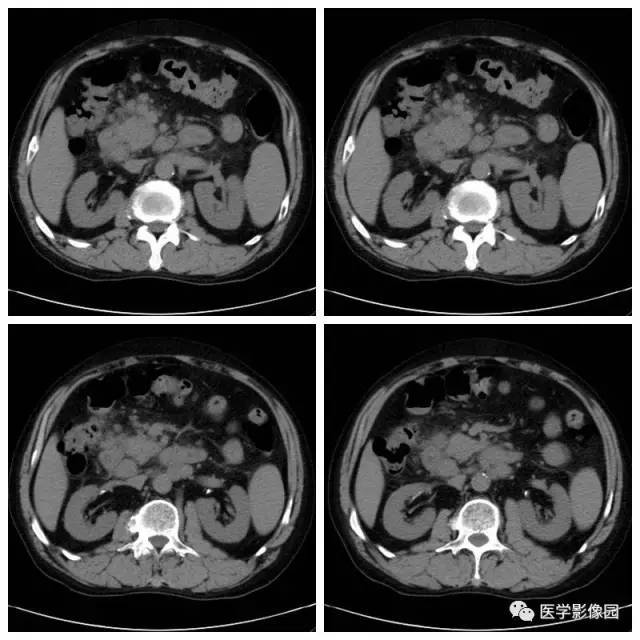

腹腔及腹膜后多发肿大淋巴结,会是什么呢

腹腔及腹膜后多发肿大淋巴结,会是什么呢